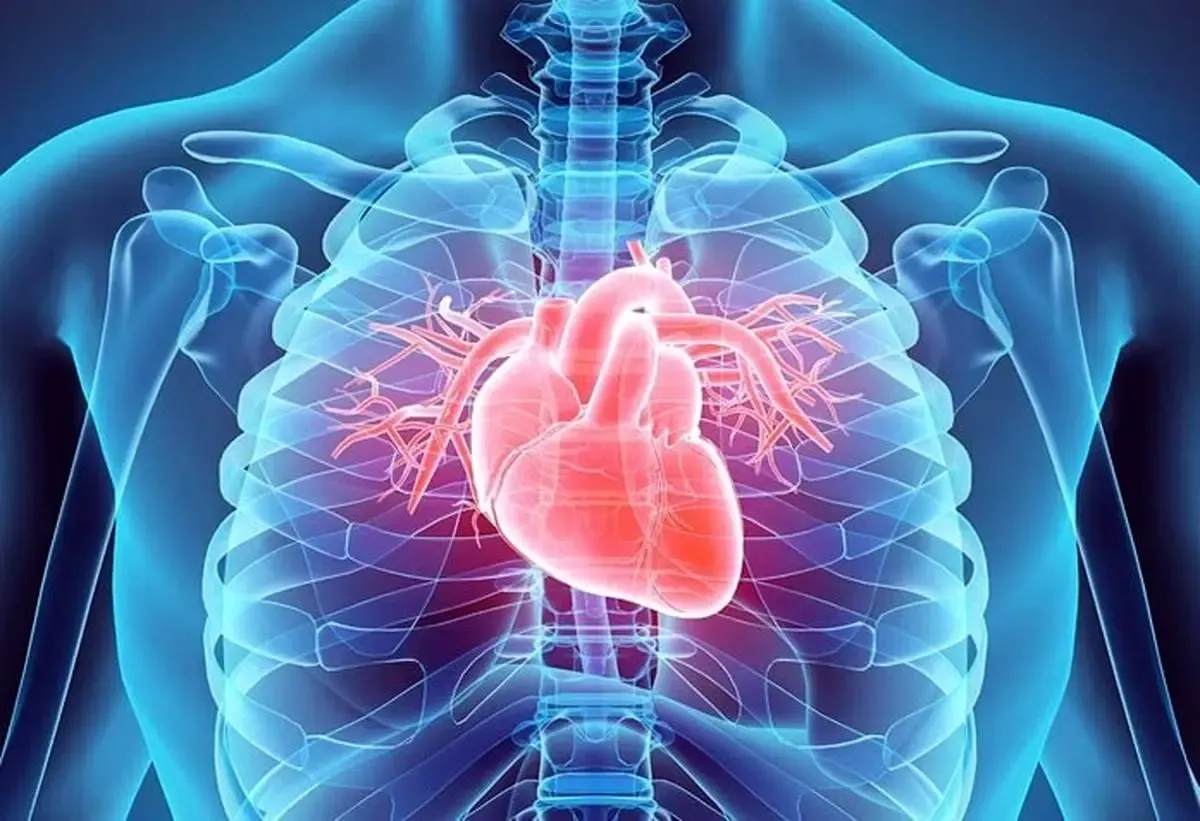

به گزارش آرمان ملی آنلاین ، بر اساس این مطالعه که در نشریه انجمن قلب آمریکا منتشر شده است، فشار شغلی با افزایش احتمال ابتلا به شایعترین نوع ضربان قلب نامنظم (آریتمی قلبی) ارتباط دارد.

متخصصان سوابق پزشکی حدود ۶۰۰۰ بزرگسال شاغل در بخش اداری و همینطور دادههای ۱۸ سال بعد را بررسی کردند. یافتهها نشان داد کارمندانی که گفتند تحت فشار شغلی بالایی بودهاند ۸۳ درصد بیشتر در معرض خطر ابتلا به فیبریلاسیون دهلیزی قرار دارند که شایعترین نوع آریتمی یا ضربان قلب نامنظم است.

کارمندانی که گزارش دادند احساس «نامتوازنی تلاش و پاداش» دارند ــ به این معنا که فکر نمیکنند عملکردشان به شکلی منصفانه با «حقوق»، «قدردانی» یا «امنیت شغلی» جبران شده باشد ــ ۴۴ درصد بیشتر احتمال دارد به فیبریلاسیون دهلیزی مبتلا شوند.

این خطر در کارمندانی که همزمان احساس فشار کاری بالا و نامتوازنی تلاش و پاداش داشتند ۹۷ درصد افزایش مییابد.

علائم فیبریلاسیون دهلیزی سرگیجه، خستگی، تنگی نفس، ضربان قلب نامنظم یا احساس تپش یا تندتند زدن قلب را شامل میشود. فیبریلاسیون دهلیزی همچنین میتواند خطر حمله قلبی یا سکته مغزی را افزایش دهد.